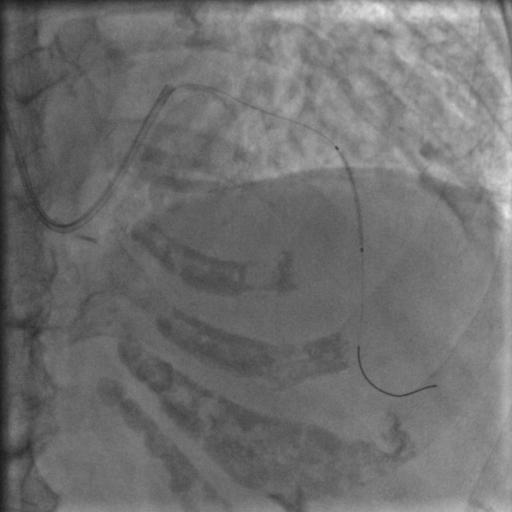

按照常规,更换指引导管,送入导丝,顺利通过闭塞病变到达前降支远端,很顺利,D-to-B时间70分钟,达标,曙光在前头。

图5

导丝过了之后常规造个影:

图6

没通,这个也很正常,急性冠脉闭塞导丝过了之后血栓还堵着是很经常的事,按常规打点欣维宁,考虑到她86岁,打入8ml欣维宁,造影: